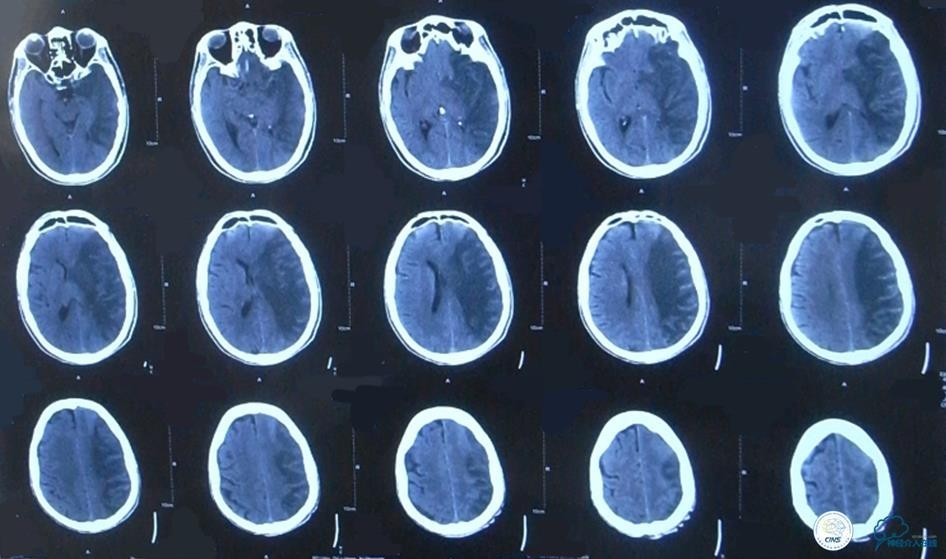

▼颅脑CT

▼2015-06-13颅脑CT

患者症状稳定,遗留有失语及右侧肢体活动不灵。